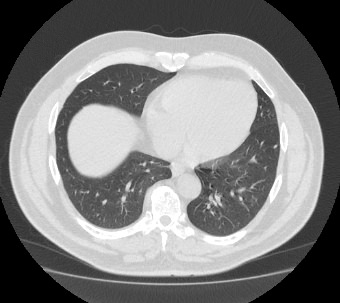

Мультиспиральная компьютерная томография органов грудной клетки представляет собой рентгеновское исследование костных структур грудной клетки, легочной ткани, бронхиального дерева, органов средостения.

Информативность МСКТ органов грудной клетки дополняет функциональная проба, то есть методика проведения сканирования на вдохе (инспираторная КТ) и на выдохе (экспираторная КТ). При выполнении КТ на вдохе с задержкой дыхания удается добиться максимального контраста между наполненными воздухом легкими и более плотными структурами, такими как плевра, стенки бронхов и кровеносные сосуды. Кроме того, на фоне пневматизированных легких хорошо видны очаговые и диффузные патологические изменения.

При экспираторной пробе (пробе на выдохе) можно выявить воздушные ловушки (то есть стойкое повышение пневматизации легочной ткани) на фоне пневмонитов, бронхиолитов, обструктивных заболеваний легких, эмфиземы.

Компьютерная томография в нашей клинике проводится на современных мультиспиральных томографах, которые производят тончайшие срезы исследуемой области и создают трехмерные изображения всех структур грудной клетки высокой четкости и контрастности. Увеличенное количество детекторов, которыми оснащены аппараты, обеспечивают быстрое сканирование зоны исследования при минимальных дозах рентгеновского облучения.